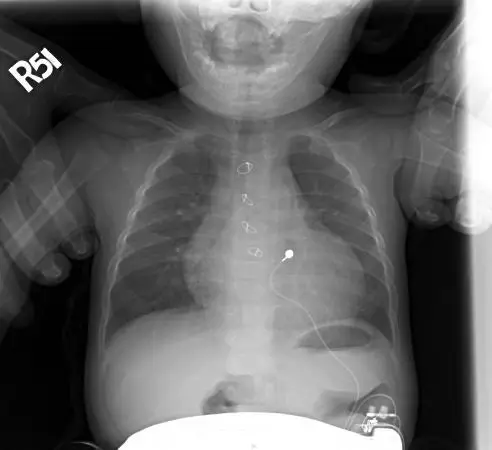

1歲小男孩,突然臉色蒼白,冒冷汗,父母描述過去因心跳慢,曾於出生不久接受某種手術,身體診查發現心跳只有 56 次/分,緊急 CXR 如下。此小男孩最可能過去接受過何種手術?

本題 CXR 為嬰幼兒正面胸部 X 光片,右側標有 R51 方向標記。影像關鍵發現如下:

- 心律調節器脈衝產生器(pulse generator):可見於影像下方腹部位置(上腹部/腹部皮下),為一金屬密度之矩形裝置,這是嬰幼兒電池包通常放置的位置(因嬰幼兒胸腔太小,脈衝產生器多置於腹壁皮下)

- 心外膜電極導線(epicardial leads):影像中可見細微的放射不透明金屬導線,從腹部裝置延伸至胸腔,連接至心臟表面

- 心臟大小:心臟輪廓在正常範圍,無明顯心臟肥大

- 肺野:雙肺野清晰,無明顯充血或肺水腫跡象

此影像所見為嬰幼兒心外膜心律調節器(epicardial pacemaker)植入後之典型 X 光表現,脈衝產生器置於腹部皮下,電極導線縫附於心臟外膜(心外膜),與成人經靜脈(transvenous)植入方式不同。